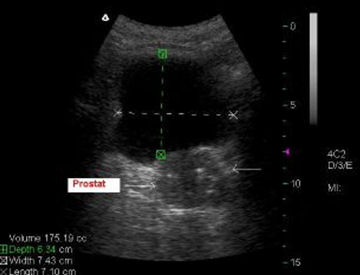

Urinary system sonography